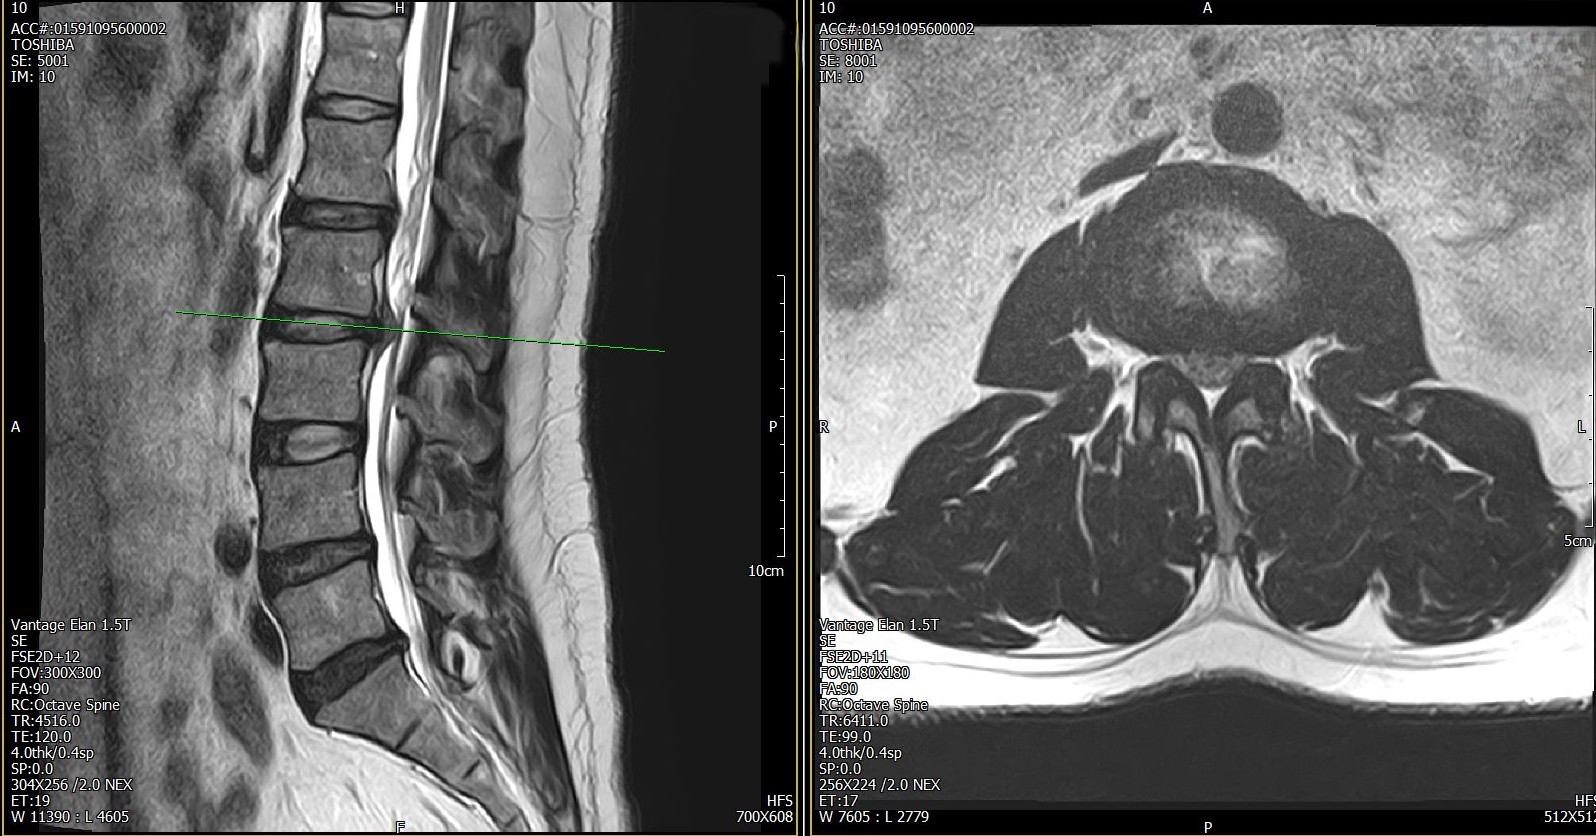

허리디스크

2021년에 허리 디스크가 발병했다. 2-3번 디스크가 파열됐다. 한 달 정도는 침대에서 거의 움직이지 못할 정도로 심각했다. 고통도 극심했지만 사람 구실을 하지 못할 수도 있다는 공포가 더 심했다. 세월이 흘러서 일생 생활에 무리가 없는 수준까지 회복되었지만 후유증은 여전히 남아있다. 달리기 같은 운동은 하지 못하고 무리하면 무릎 주변으로 방사통이 있다. 병원에 가도 환자 취급을 받지 못하고 운동으로 극복해보려고 했지만 번번이 실패했다. 길을 잃은 느낌이다.

최초 진단시 촬영했던 MRI 사진, 2020.11.17